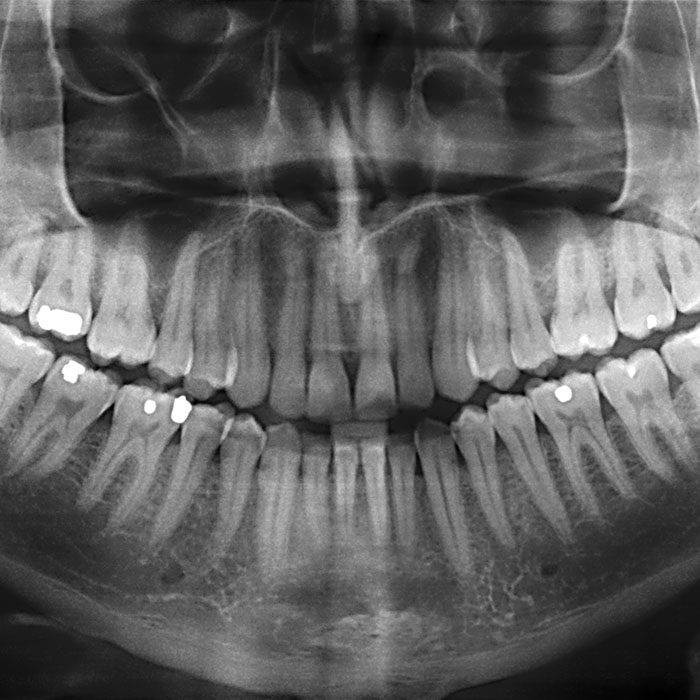

• Dental X-rays of the affected tooth and the surrounding bone

To ensure accuracy, we might also take an X-ray during the procedure, and the length of the procedure will vary depending on which tooth it is, the complexity of the root structure, and your individual needs as a patient.